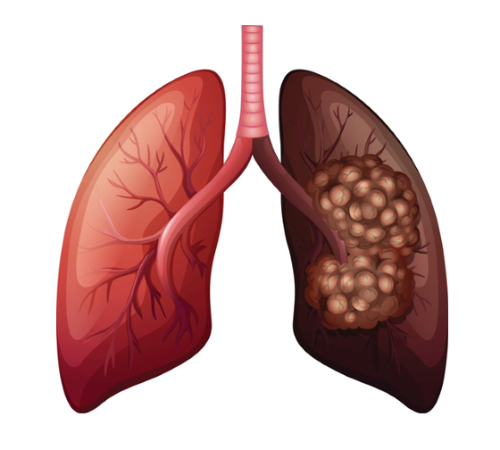

폐암이란

폐암이란 우리 몸의 폐에 생긴 악성 종양을 말합니다. 원발상 폐암이라고 해서 폐 자체에서 발생하거나 다른 장기에서 생긴 암이 폐로 전이될 수도 있습니다. 원발성 폐암의 종류에는 암세포의 형태와 크기에 따라 비소세포 폐암과 소세포 폐암으로 구분합니다. 폐암의 80~85%는 비소세포폐암에 해당하며 이것은 다시 선암(샘암), 대세포암, 편평상피세포암 등으로 나뉩니다. 그리고 소세포폐암은 대체로 악성도가 높아 발견되었을 때 이미 림프관 또는 혈관을 통하여 다른 장기나 반대편 폐, 종격동, 기관, 식도, 대동맥, 양쪽 폐 사이의 공간으로 심장 등으로 전이되어 있는 경우가 많습니다.